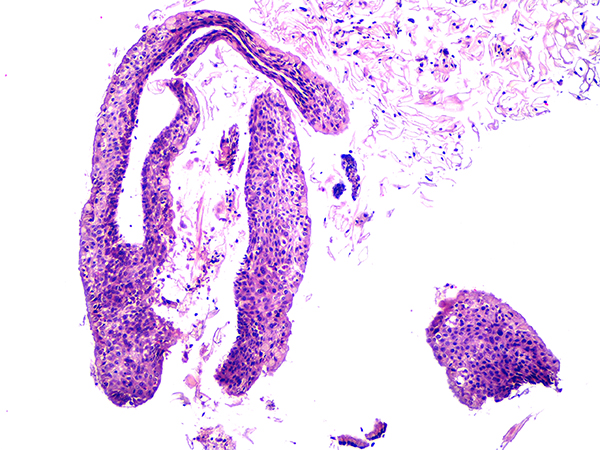

Case 2

Soft Bx CIN 2 10x - Low Power |